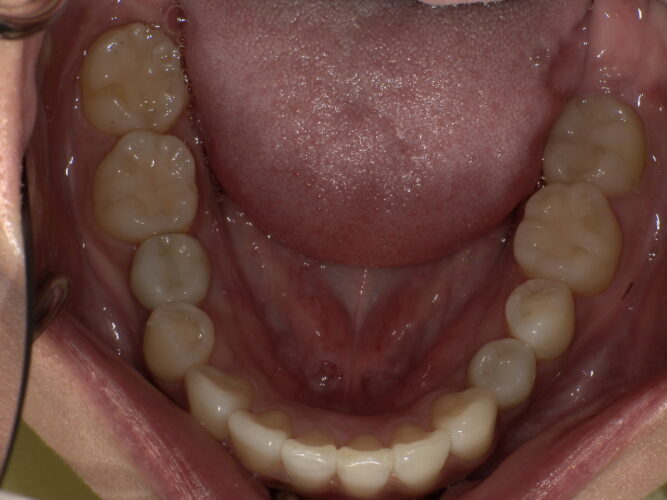

インプラント手術後

インプラント手術し両側にインプラントを埋入しています。